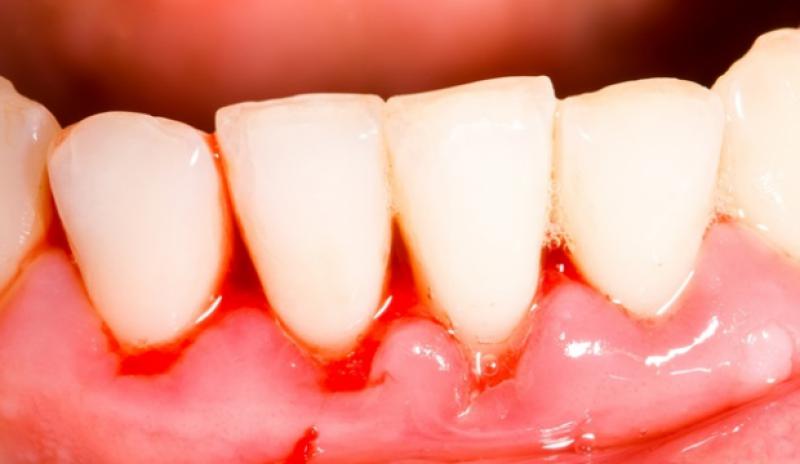

Eğer yaşadığınız kanama yalnızca lekelenme şeklindeyse, bu bazı kadınlar için gebelik döneminde sıkça karşılaşılan bir durumdur. Ancak, eğer kanama yoğun ve sürekli ise, bu durum daha fazla değerlendirilmesi gereken bir durumu işaret edebilir.

Kanama durumu, rahim veya vajinada bir sorun olabileceği anlamına gelebilir. Ancak bu, mutlaka böyle olduğu anlamına gelmez. Kesin bir değerlendirme için doktora başvurmanız en doğrusu olacaktır.